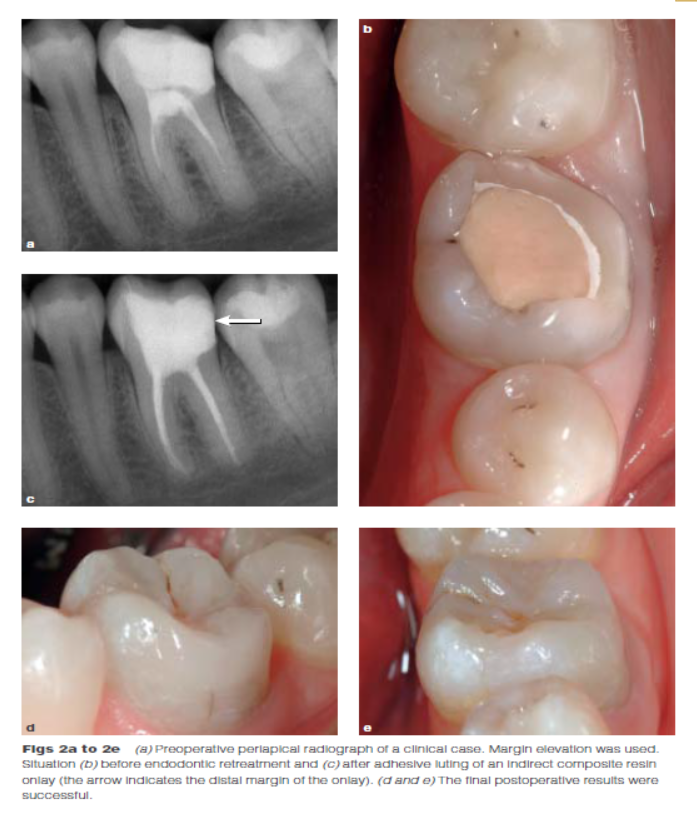

DME是用一個改良彎曲的成型片接堆放復(fù)合樹脂來提升齦壁高度,使其能夠在修復(fù)過程中使用橡皮障封閉邊緣,可以在固化前適當(dāng)?shù)囊瞥嘤嗟膹?fù)合樹脂。DME應(yīng)該在即刻牙本質(zhì)封閉(IDS)之后,在使用橡皮障的條件下,且僅在邊緣可被改良的成型片適當(dāng)隔離時直接獲得。否則,這個技術(shù)不能使用。在最終取印前,需要拍攝咬合翼片來評估復(fù)合樹脂在齦邊緣區(qū)域的密合度(有無懸突或缺陷)。同樣需要仔細隨訪來評估軟組織的健康和是否需要外科手術(shù)干預(yù)。只要可能,在牙髓治療前就應(yīng)通過DME術(shù)制造假壁,使根管治療更完善(圖2、3)。圖4展示了一個典型DME術(shù)的適應(yīng)癥。

因為當(dāng)使用IDS技術(shù)時,提升后的邊緣需要小心的對復(fù)合樹脂基底進行清潔,通過噴砂、酸蝕沖洗牙釉質(zhì)、涂布粘接劑?(As when using the IDS technique, delivery of the restoration on an elevated margin requires careful cleaning of the existing composite resin base using airborne-particle abrasion followed by etching/rinsing enamel and application of adhesive risin.) Gresnigt et al認為在復(fù)合樹脂甚至是陳舊的復(fù)合樹脂修復(fù)體上粘接間接修復(fù)體并不會影響其壽命。